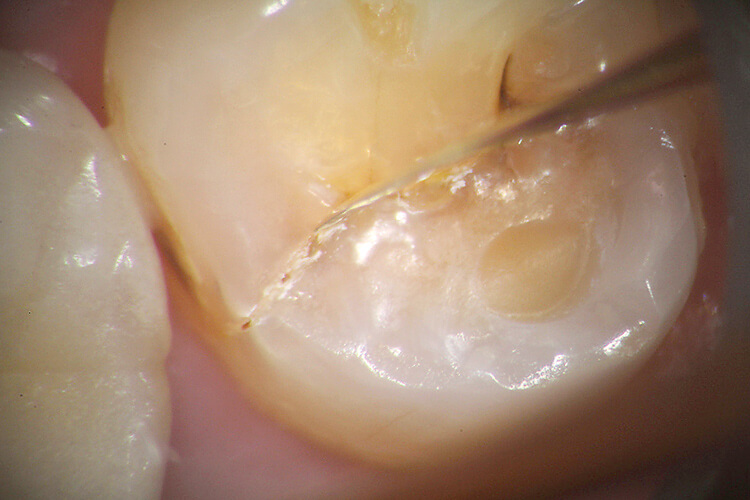

私の臨床において、マイクロスコープはなくてはならないものとなっている。目視では見落としていた病変(歯牙の破折、軟化象牙質、残髄)を見つけ出すことができ(図1)、 治療(支台歯形成、レジン充填、Endo、歯周外科)においては、今まで目で確認したものとして治療を進めていたことが、マイクロスコープによって拡大して確認し、修正できるようになった(図2、3)。

図1 目視では見落としがちな病変でも、マイクロスコープならはっきり分かる。歯牙が破折しているのが分かる。

図3 マイクロスコープの根管治療への応用。上顎左側第二大臼歯の近心頰側根をマイクロスコープ下で超音波チップを用いて選択的に歯質を落として行った根管拡大。